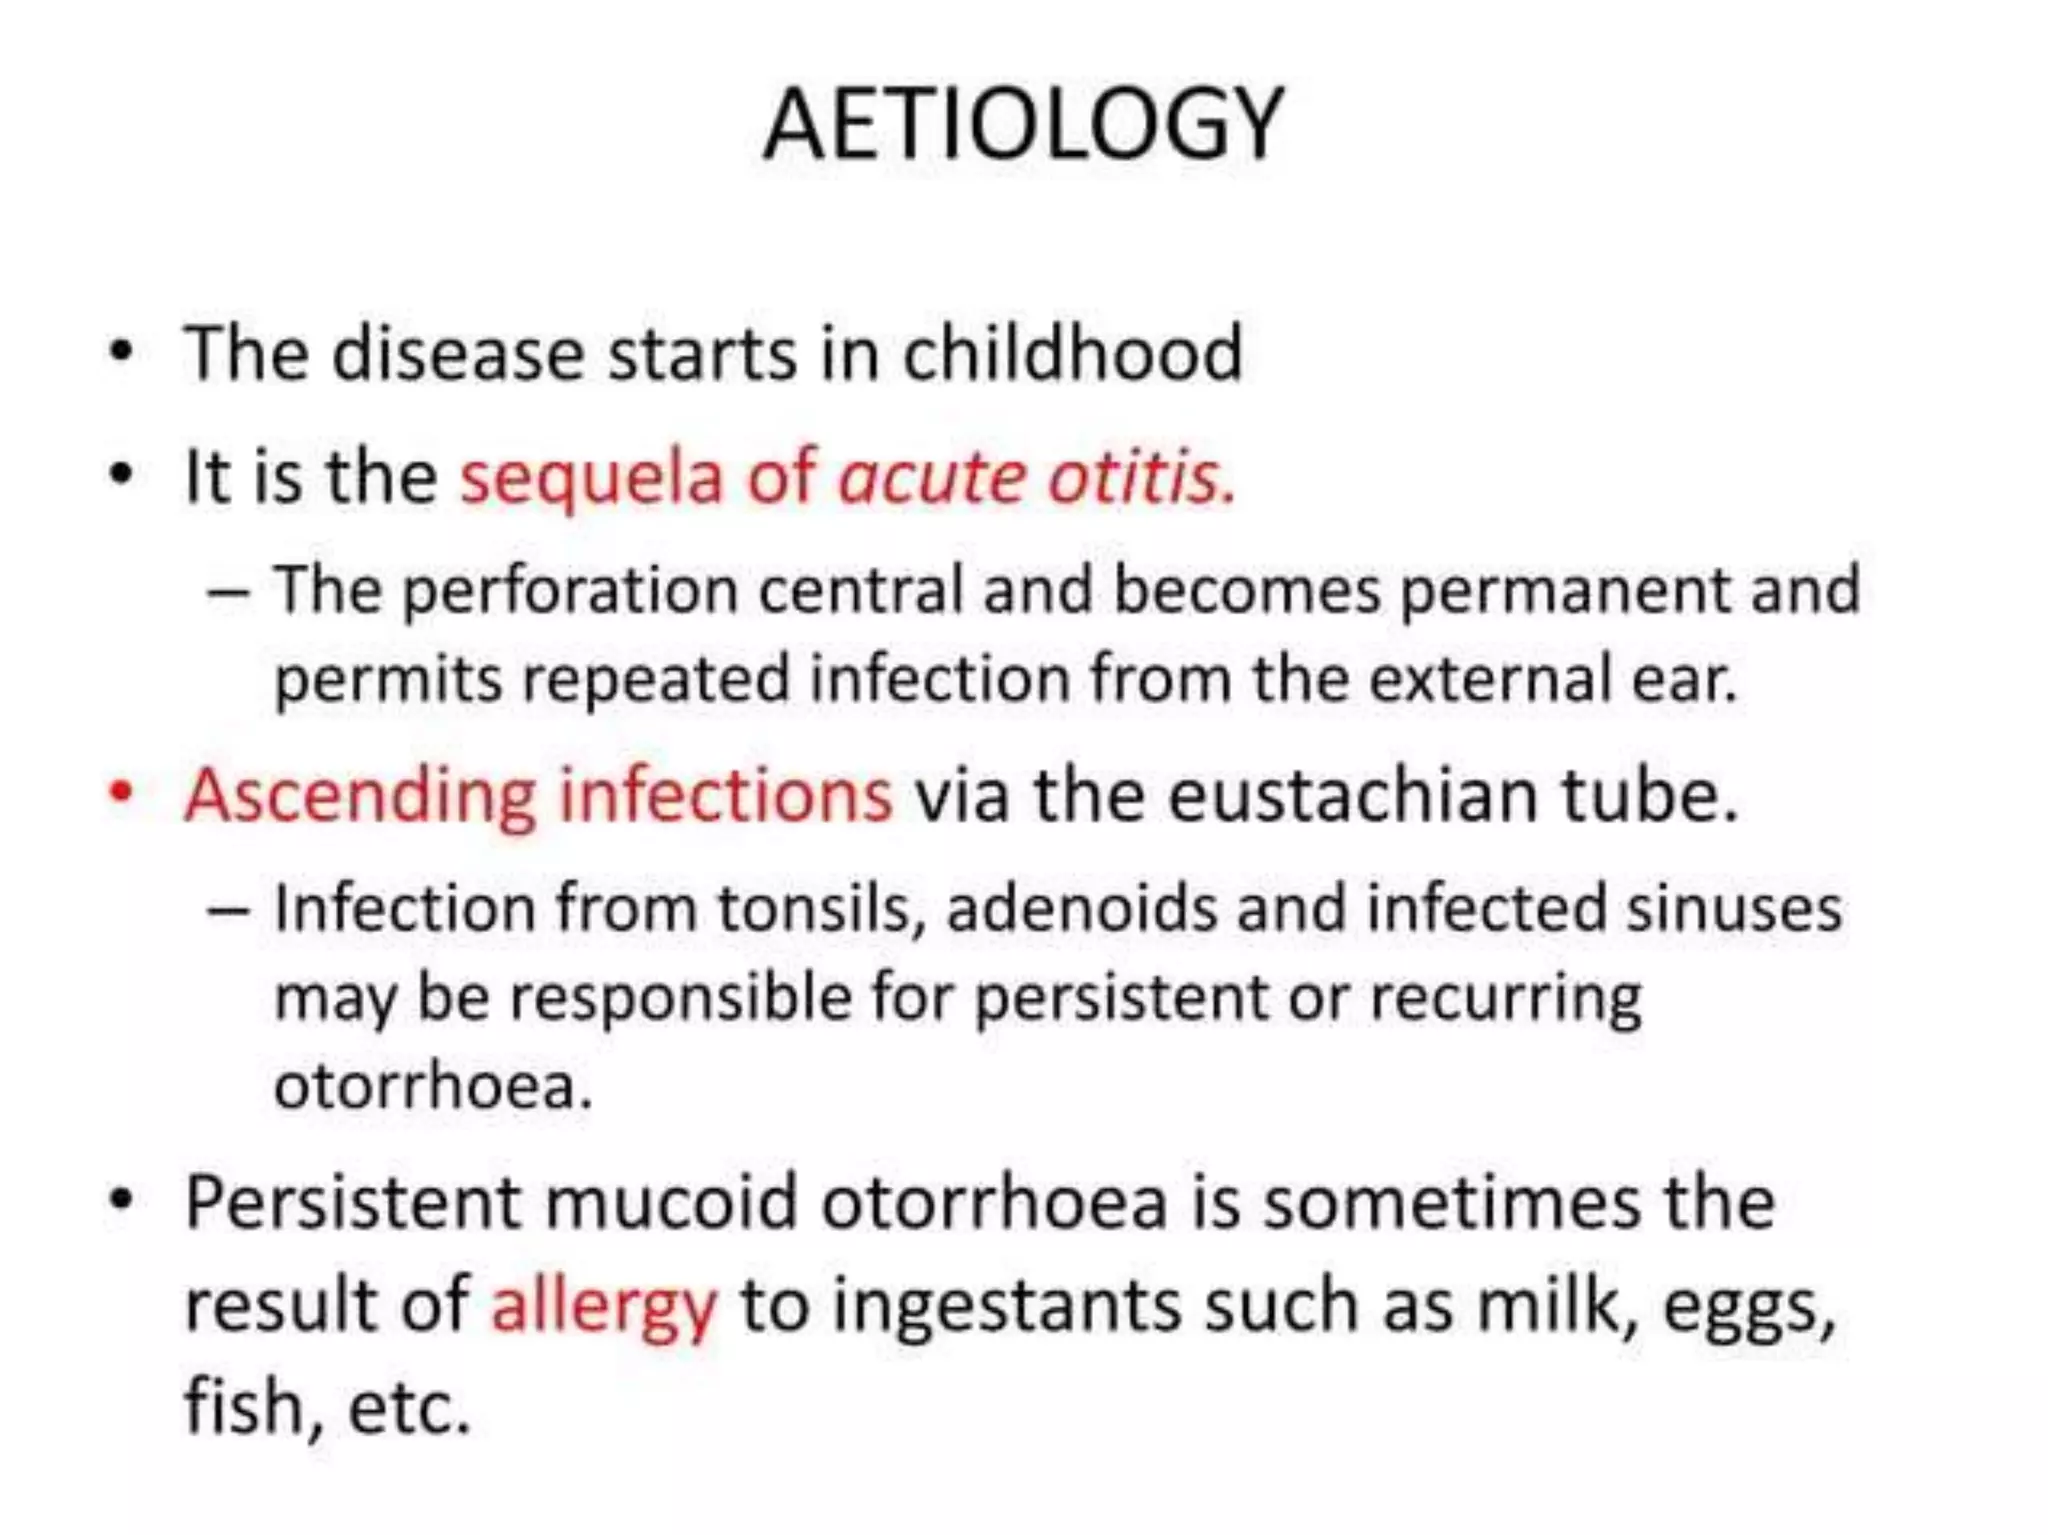

Chronic otitis media is a chronic inflammation of the middle ear and mastoid cavity that presents with recurrent ear discharge through a perforated eardrum. It has several subtypes depending on the state of the eardrum perforation and epithelium. It can be caused by prior acute otitis media, genetics, environment, eustachian tube issues, gastroesophageal reflux disease, craniofacial abnormalities, or immune deficiency.